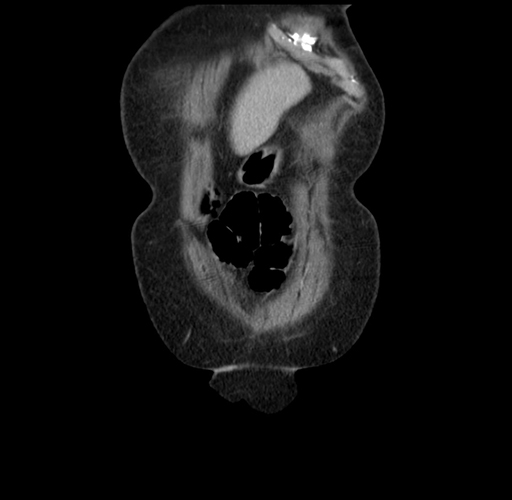

Coronal Venous